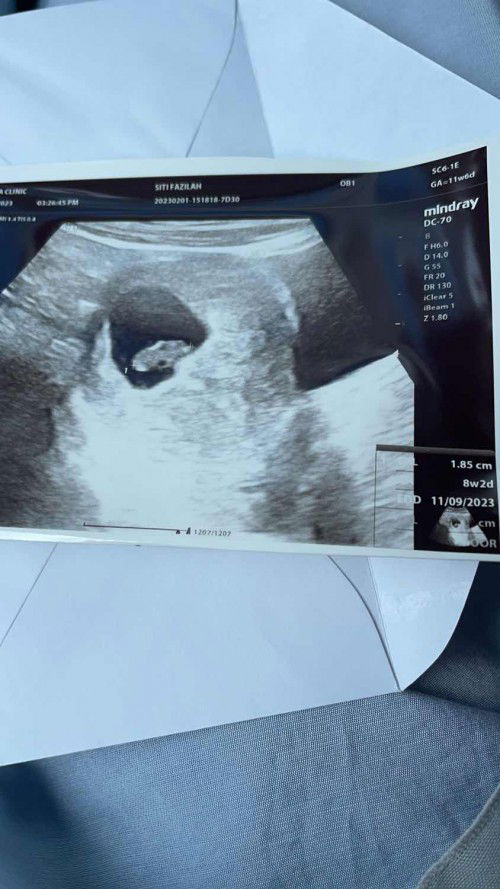

8 weeks tak ada heat beat baby

Ikut kiraan dokter saya dah 12 minggu hari ni. Tapi scan baru 8 week. Tak ada heart beat baby lagi. jadi semalam, dari KK dr refer ke pakar hospital. hari ni pergi klinik EPAU dan buat TVS usia kandungan dalam 8 week 1 day. Tapi tak ada kesan heart beat lagi. 2 minggu lagi 16/2/23 repeat scan. Tapi dokter pesan, kalau ada bleeding ke dalam tempoh 2 minggu tu datant je ke hospital. Ada yang pernah macam saya? boleh share? sebab ni first time mengandung.. #ingintahu #firstbaby #pleasehelp #bantusharing